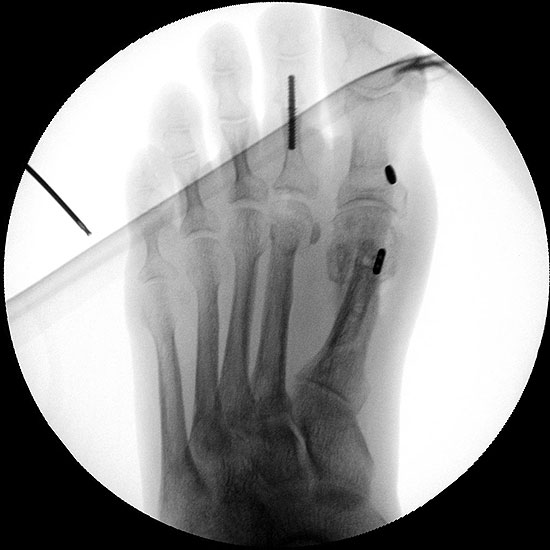

4) Augmentation der lateralen Kapsel durch ein ThightRope™ System

Eine isolierte Instabilität der lateralen Kapsel lässt sich auch mit einem ThightRope™ System (Fa. Arthrex, Naples, Florida) behandeln 17. Über ein Bohrloch im Kapselbereich des Metatarsale I und ein weiteres Bohrloch in der Grundphalanx wird der Faden des ThightRope™ Systems zur Verstärkung der lateralen Gelenkkapsel eingezogen (Abbildung 12 und 13). Es ist darauf zu achten, dass der Faden in der Gelenkachse verläuft, da ansonsten die Grundphalanx nach dorsal oder plantar gezogen wird mit entsprechender Bewegungseinschränkung.